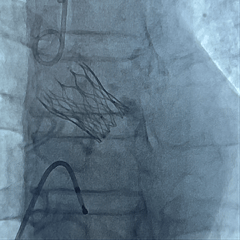

25号瓣膜释放至全展开

造影评估:瓣膜位置可,形态稳定

多角度评估,瓣膜位置可

脱钩后造影,瓣膜位置可,几乎无瓣周漏

主动脉瓣位为人工瓣回声,瓣架位置固定,瓣叶活动良好,未见赘生物,未见瓣周漏。余瓣膜形态及运动未见异常。

主动脉瓣前向最大流速201cm/s,Pg16 mmHg。